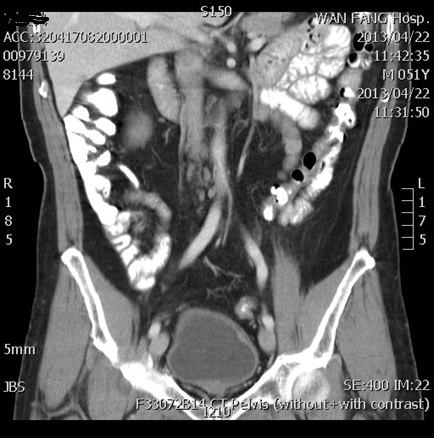

案例3:曾 OO 概況

• 曾先生 51歲男性,無罹患任何慢性疾病亦無不良生活習慣,任職資訊科技業。

• 105年農曆過年前1月突然出現血尿,

• 電腦斷層攝影及膀胱鏡檢查,診斷為膀胱原位癌

• 病理報告為臨床第一期膀胱癌,其癌細胞為高分化程度並已經侵犯固有層,在臨床上屬於高度容易復發且易進展為肌肉層侵犯的膀胱泌尿上皮細胞癌

• 在本院癌症團隊的討論後,建議接受膀胱內化療灌注輔以區域深層熱療,故3月起接受此每周一次共5周的療程

• 105年5月再次接受經尿道鏡膀胱腫瘤切除手術評估,結果完全無殘留癌細胞。

• 每3個月接受一次尿液細胞學及膀胱鏡檢查,歷經18 個月仍無癌症復發現象